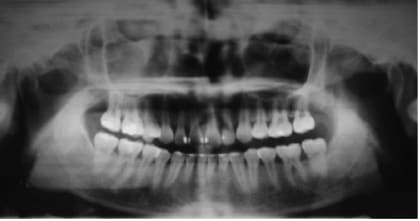

J'ai complété le schéma que tu avais posté plus haut dans le plan sagittal, fais comme ça dans un plan frontal au niveau 48 et tu verras.

Daniel